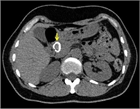

1. 膵管内の結石(膵石)を認めた場合と、膵全体に分布する複数かつびまん性の石灰化を認めた場合は慢性膵炎と診断できる(推奨度1)